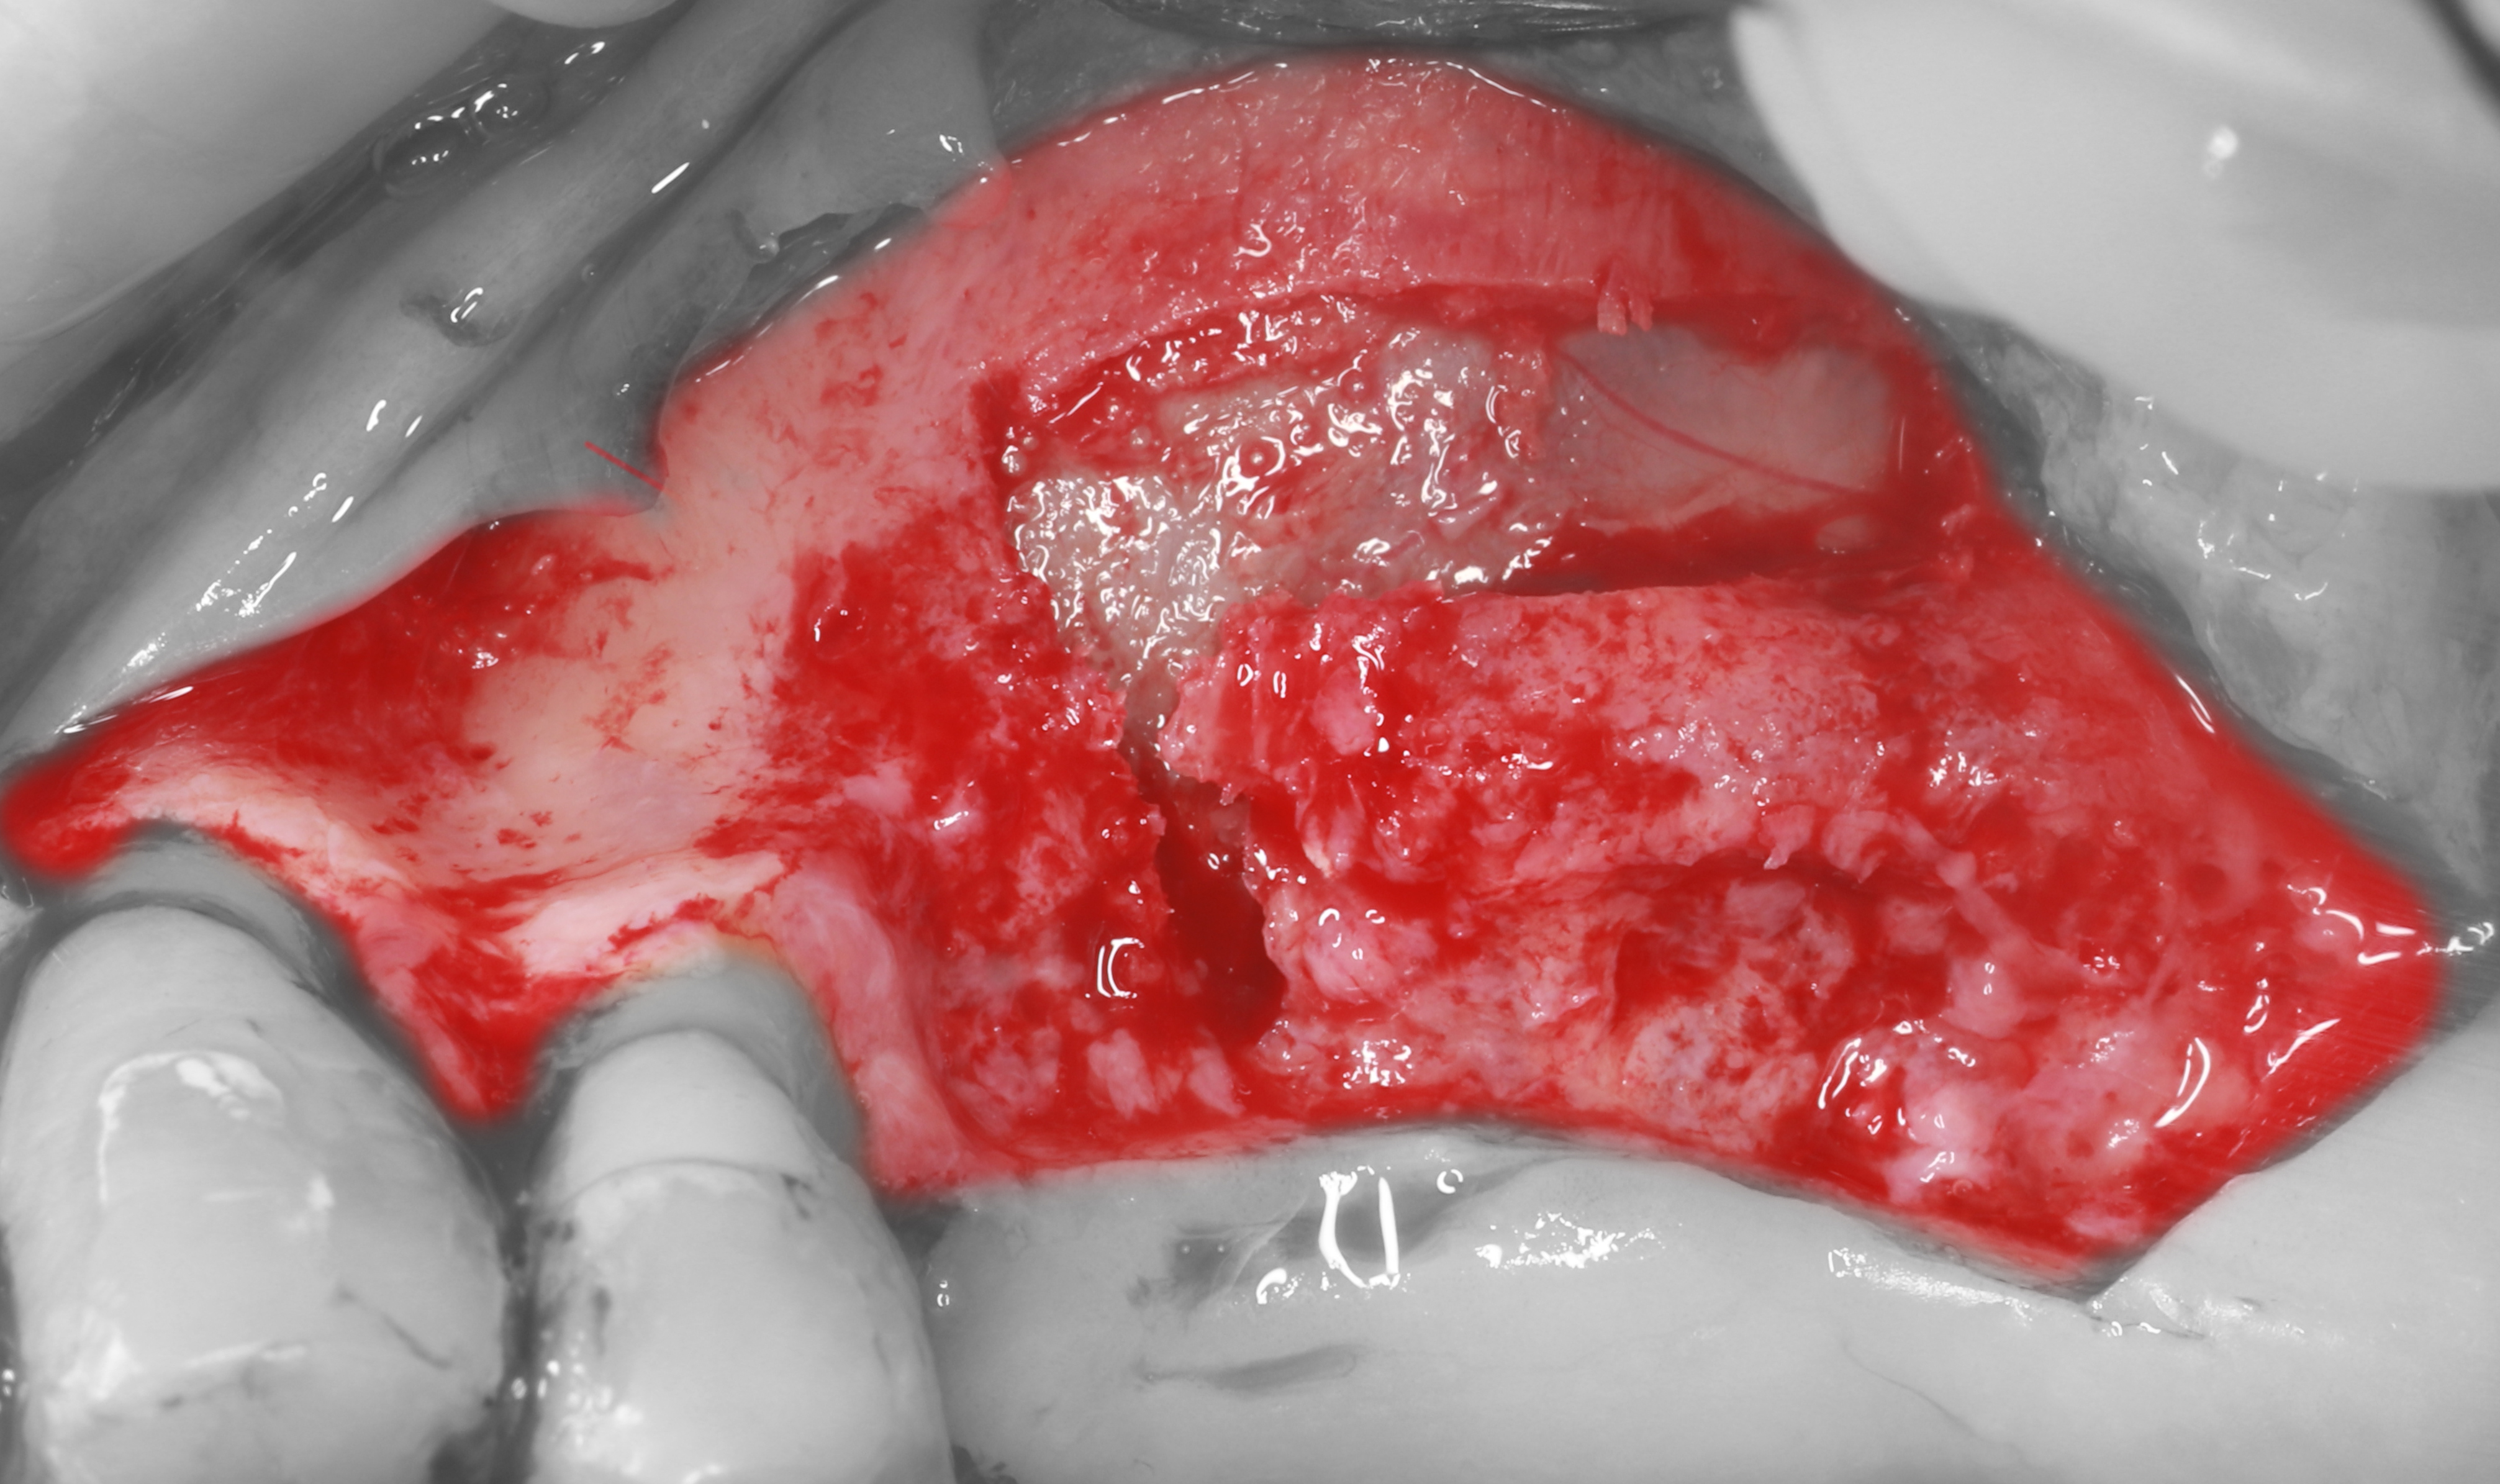

1) Дано: удаление зубов 1.5, 1.6, 1.7 около 3,5 месяцев назад по причине пародонтита.

2) Проведены крестальный, мезиальный и дистальный вертикальные разрезы, отслоен СНЛ.

3) Остеотомия проведена с помощью пьезохирургического аппарата.

4) Отслоен костный блок

5) Проведена мобилизация шнайдеровой мембраны, визуализируется дефект альвеолярного отростка.